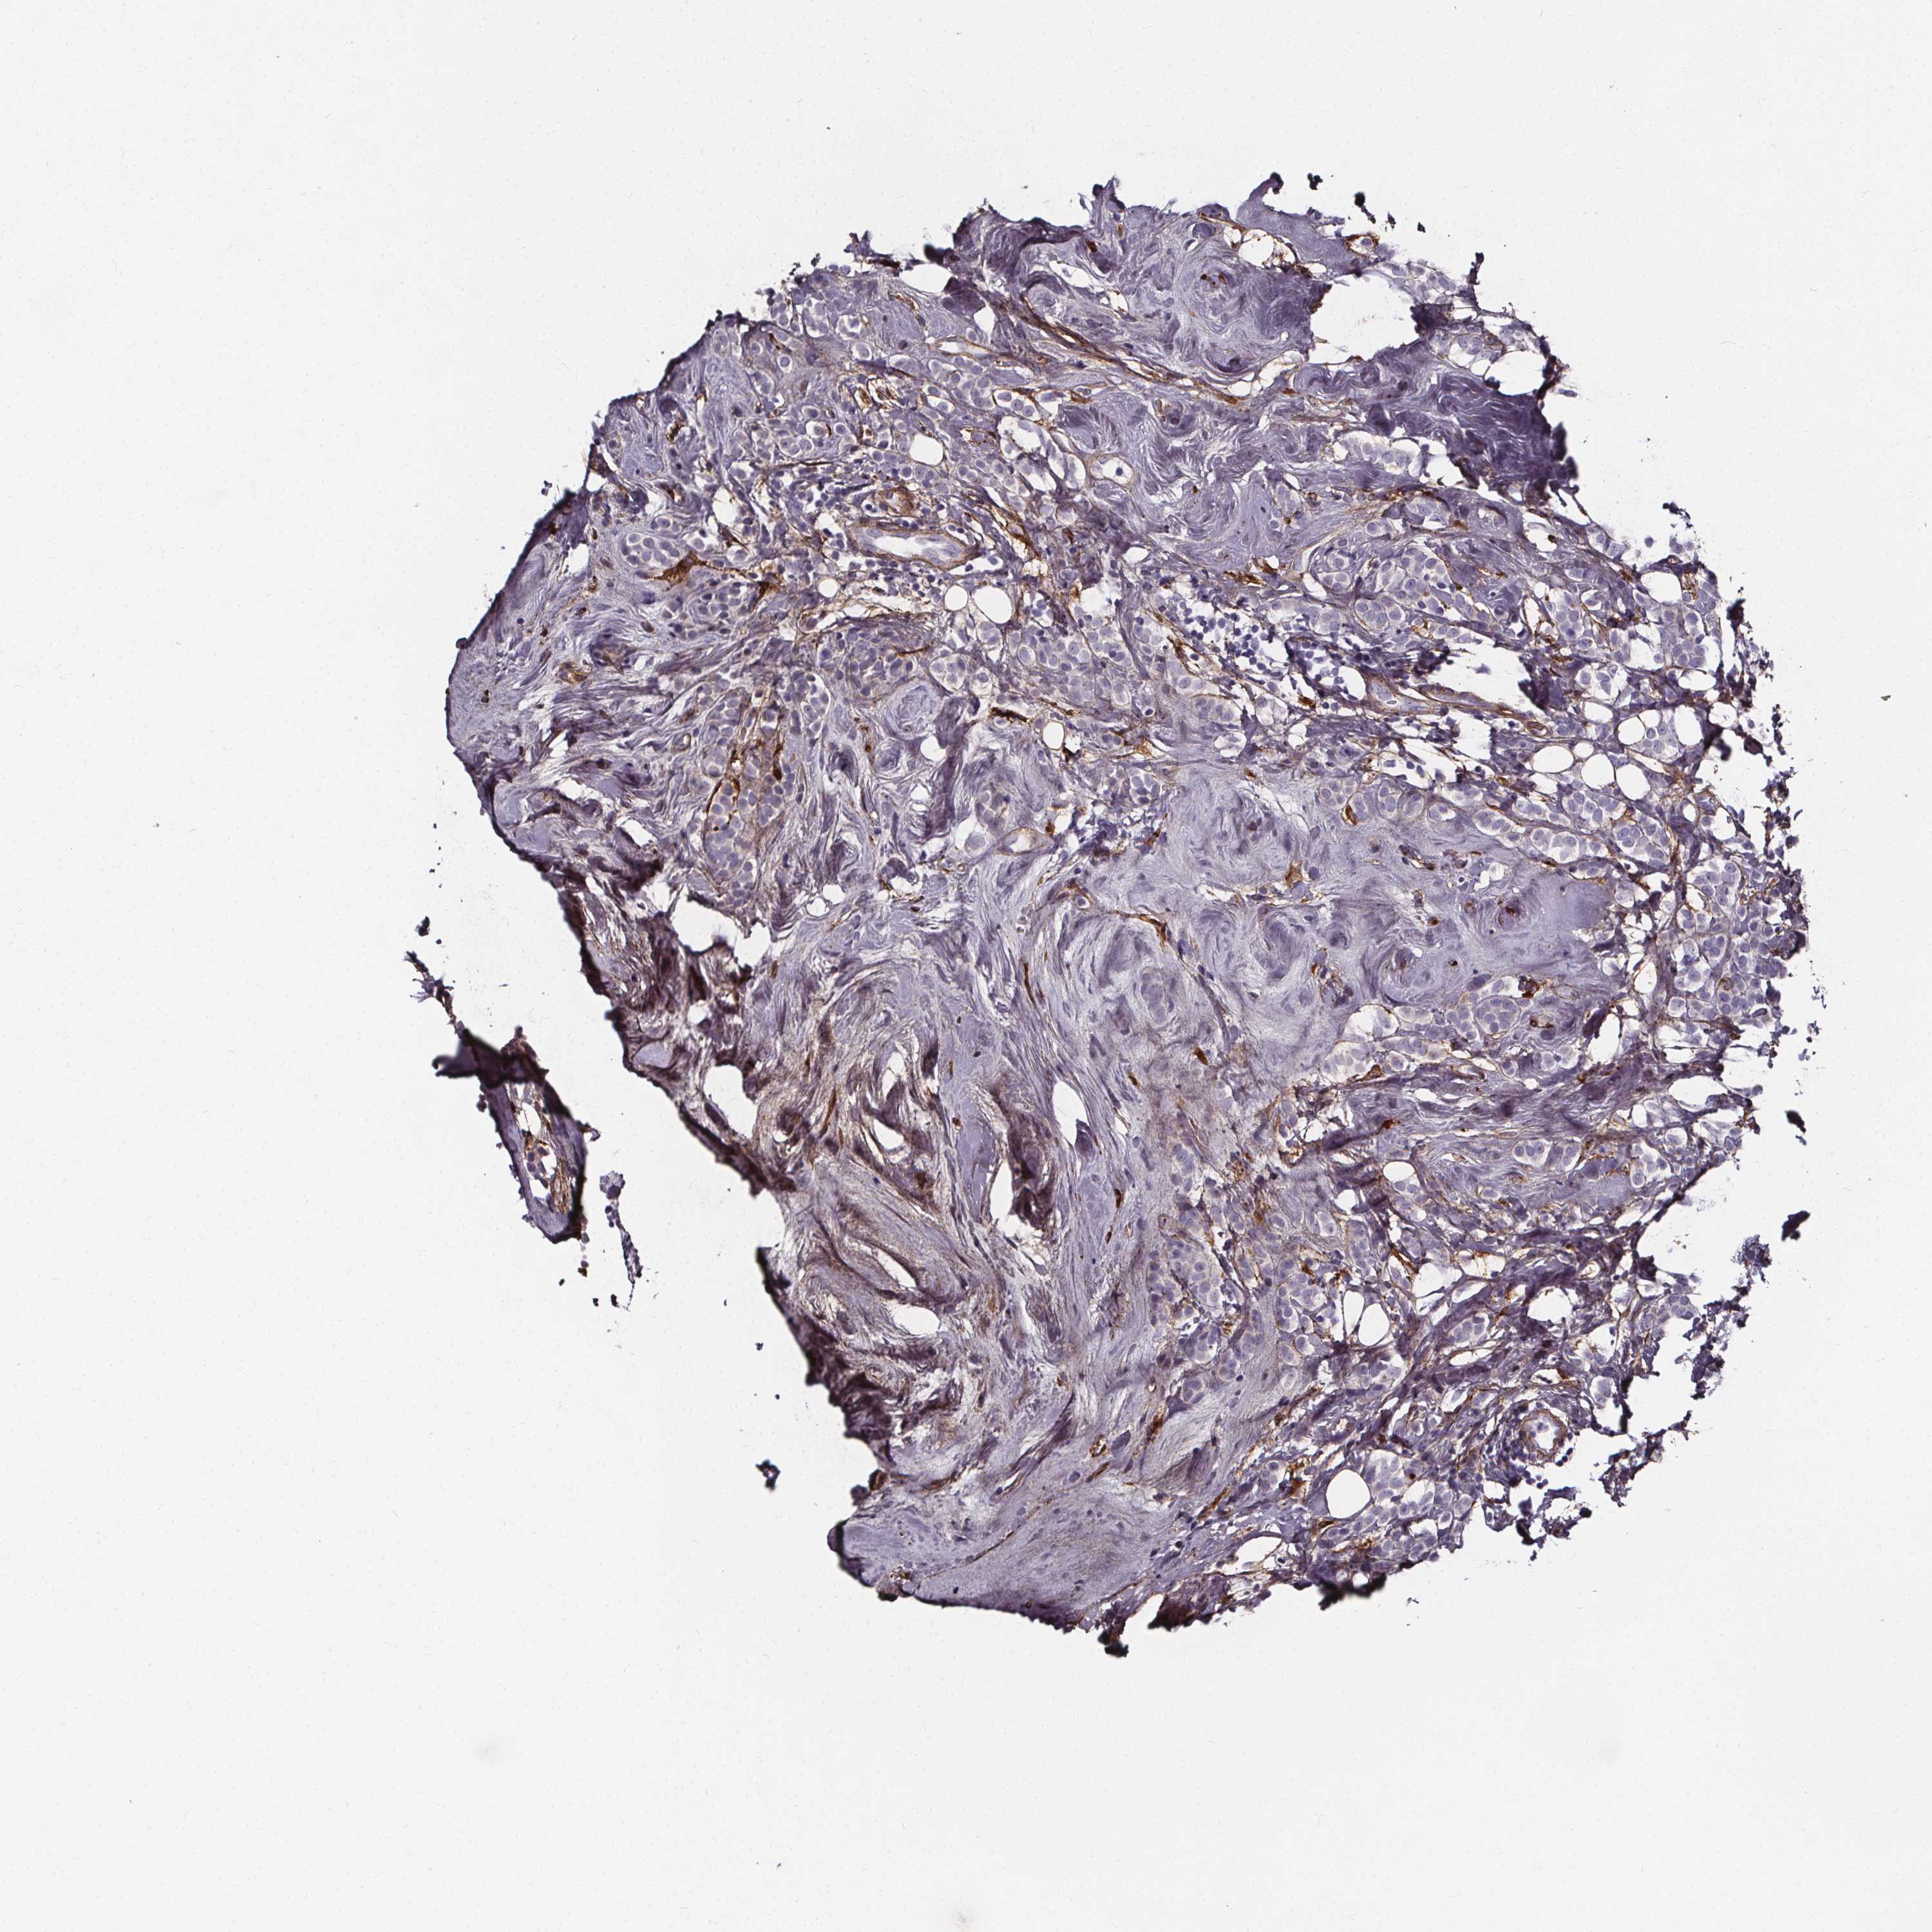

BRCA TCGA BRCA VALIDATION PROTEIN EXPRESSION